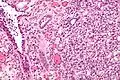

| Micrograph of a nephrogenic adenoma. H&E stain. | |

Nephrogenic adenomas are diagnosed under the microscope by pathologists. Microscopically the tumor shows closely packed small tubular structures in edematous stroma. The tubules show considerable variation in size and shape resembling convoluted tubules of the kidney. The single layer of cells lining the tubules are cuboidal with a scant to moderate amount of cytoplasm. In some areas they may have a hobnail appearance. [2]

High mag